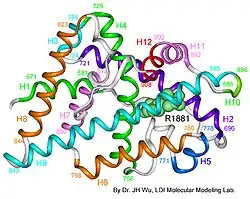

| AIS results when the function of the androgen receptor (AR) is impaired. The AR protein (pictured) mediates the effects of androgens in the human body. | |